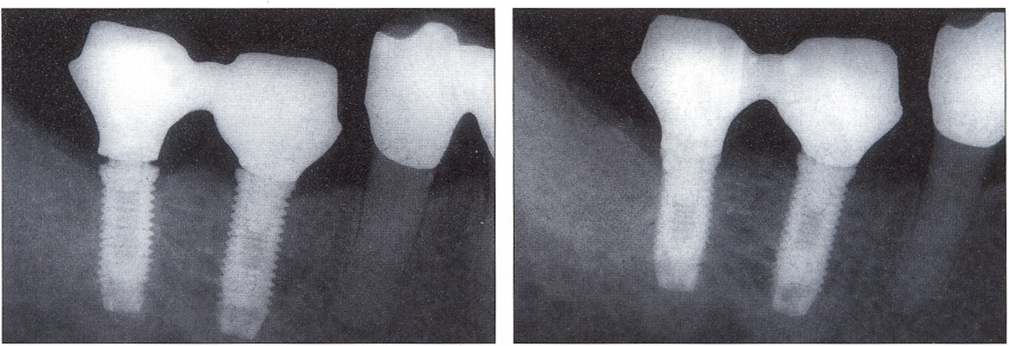

Исследование на рентгене после имплантации зубов

Раздел: Снимки-откровения